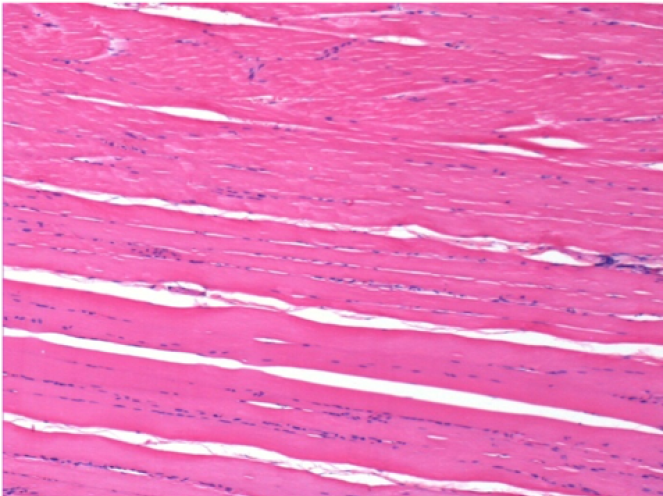

7 months (D210)after Endopeel IM Injection 0.1ml in the right pretibial muscle.

Complete Restitutio ad integrum after 7 months

L :Control 50xD210

R50X-D210